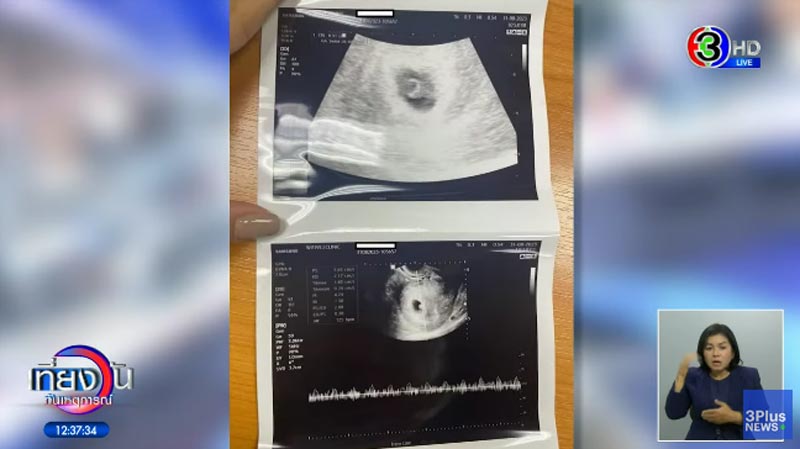

ต่อมา น้องฟ้าได้ตั้งครรภ์ แต่นักร้อง อ. ก็ไม่จบ มีไปคบกับ ไฮโซ ม. อีก และเมื่อเธอไปถามเขาเรื่องที่เธอท้องจะทำยังไง นักร้อง อ. ก็บอกว่า "ฟ้าจ๋า วันนี้ฟ้าไม่ใช่ความสุขของพี่อีกแล้วนะ พี่รักฟ้าน้อยลงแล้ว" และมีการเกลี้ยกล่อมให้เธอไปทำแท้ง เพื่ออนาคตของเขา ซึ่งสุดท้ายแล้วเธอไม่ยอมทำแท้ง แต่นักร้อง อ. ได้มีการไปพูดคุยกับแม่ และบอกว่าจะขายบ้านเพื่อไปเลี้ยงลูกเลี้ยงเมีย ทำให้เธอคิดว่าทำไมชีวิตเธอกับลูกถึงเป็นภาระของฝ่ายชายขนาดนั้น จึงคิดว่าไม่เป็นไร ถ้าเขายังรักเธออยู่ และชีวิตเขาต้องอยู่ในวงการบันเทิงและคนจะเข้าใจผิดว่ามีลูกจนไม่มีงาน จึงยอมทำแท้งในที่สุด

ด้าน นักร้อง อ. จึงพาน้องฟ้าไปทำแท้ง และนั่งรอในรถ ซึ่งหลังจากทำแท้งเสร็จฝ่ายหญิงก็คิดว่าคงไม่มีอะไรอีก เพราะเธอได้แสดงความจริงใจออกมาแล้วเรื่องยุติการตั้งครรภ์ และจะกลับไปรักกัน ถ้าพร้อมค่อยมีลูกใหม่ก็ได้ แต่สุดท้ายฝ่ายชายกลับเงียบกริบ หายหน้าไป จากนั้นน้องฟ้าก็มีอาการตกเลือดวันหนึ่ง 3-4 ครั้ง ติดต่อไปหาฝ่ายชายแล้ว นักร้อง อ. ตอบกลับมาแค่ว่า "กินน้ำเยอะ ๆ นะ ดูแลตัวเองให้ดี" และหายไปเลย บล็อกช่องทางการติดต่อทุกช่องทาง